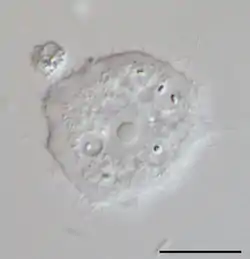

Acanthamoeba es un género de Amoebozoa, uno de los protistas más comunes del suelo y también frecuentes en agua dulce y otros hábitats. Las células son pequeñas, usualmente de 15 a 35 μm de longitud y de forma oval o triangular cuando se mueven. Los seudópodos forman un claro lóbulo semiesférico en la parte anterior y tiene varias extensiones filosas cortas a los lados del cuerpo. Esto le da una apariencia espinosa, a la cual se refiere el nombre Acanthamoeba. Los quistes son comunes y las distintas especies de Acanthamoeba se distinguen principalmente por la forma de los quistes. Muchas especies son amebas de vida libre, pero algunas son oportunistas que pueden causar infecciones en seres humanos y otros animales.

![]() Acanthomoeba sp., Trofozoíto | ||